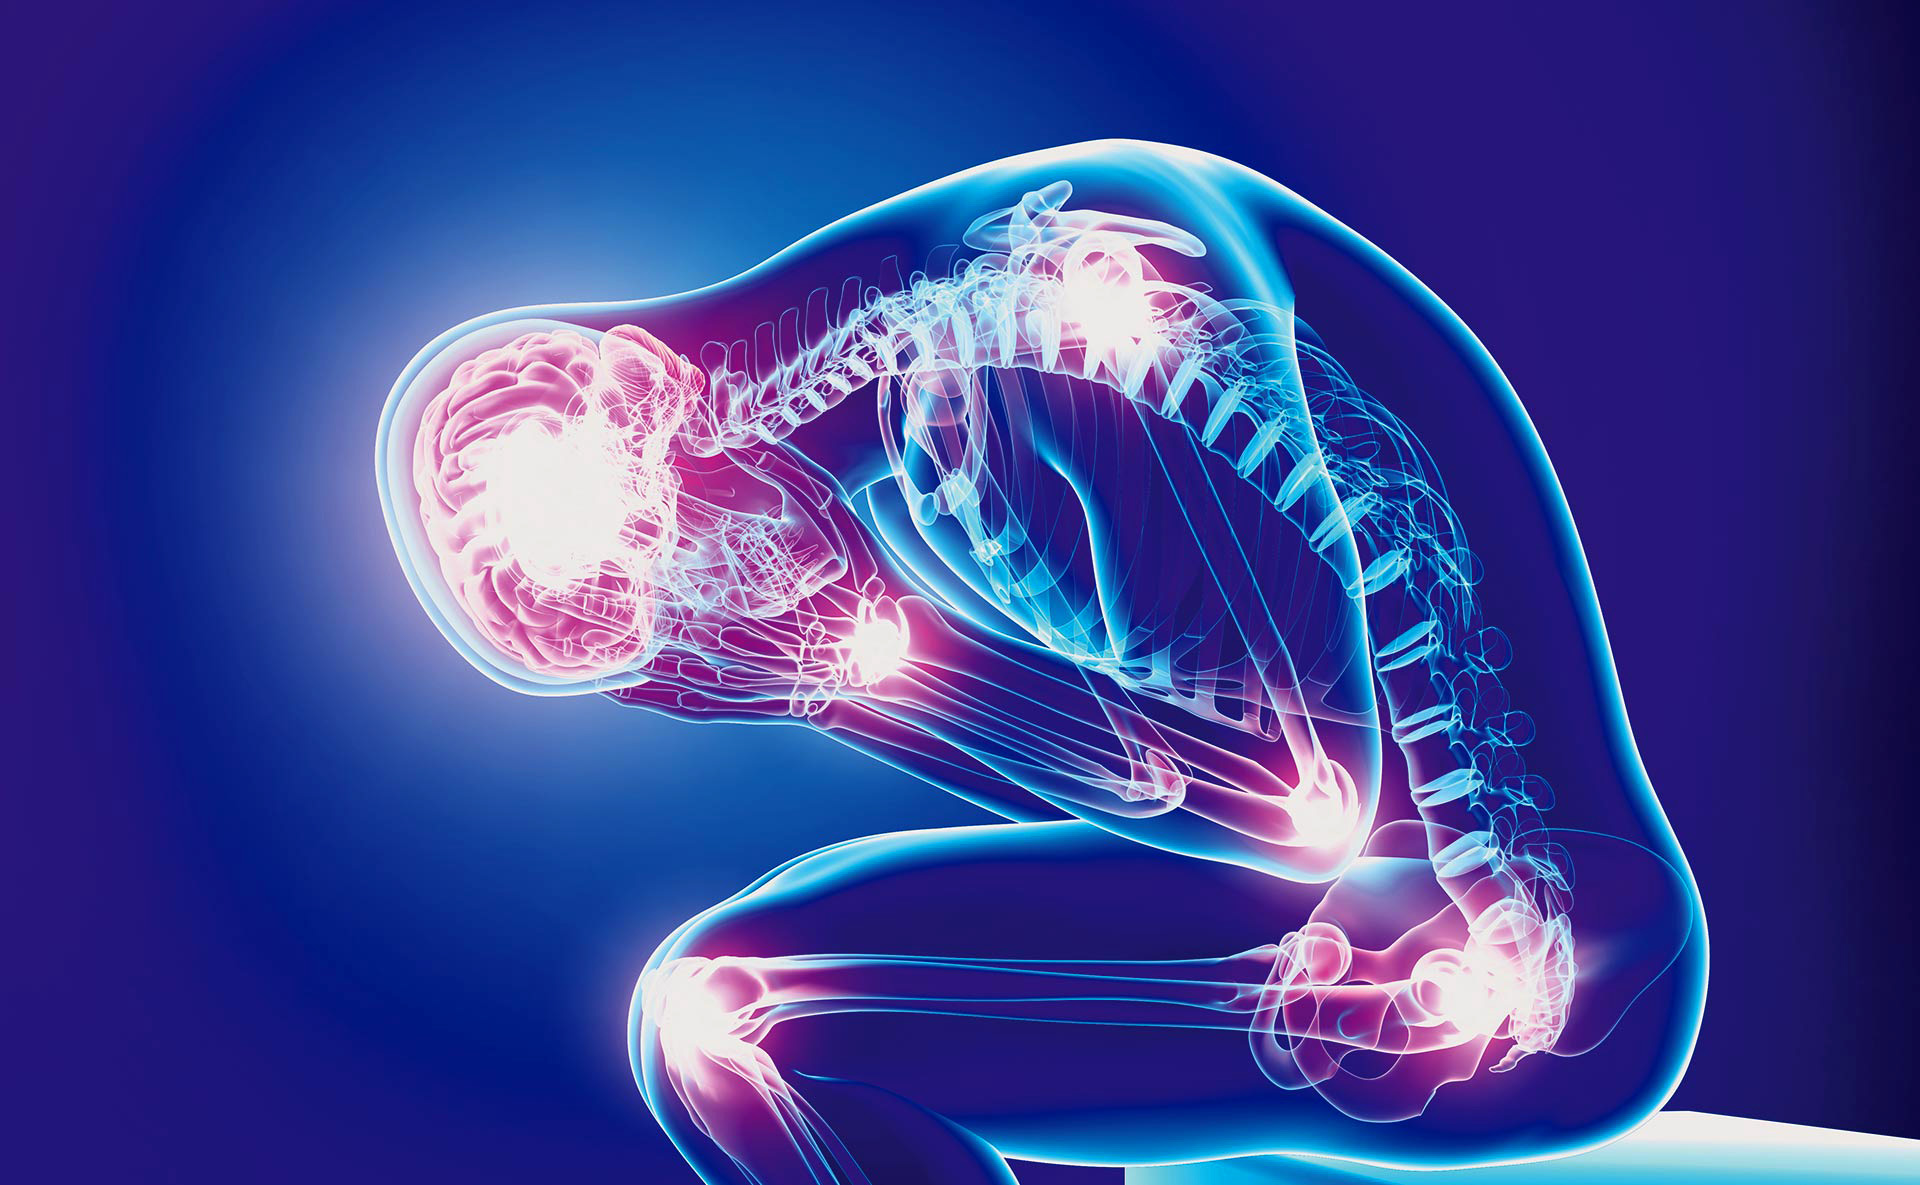

El mieloma es un cáncer de la médula ósea que acaba ‘comiéndose’ los huesos. Es difícil de diagnosticar.

La enfermedad deteriora los huesos por el mal funcionamiento de las células plasmáticas de la médula

Uno de los problemas anímicos de este cáncer es el hecho de que se pase por varios periodos de remisión y recaída. El temor a su reaparición tiñe de angustia la vida de los pacientes. Además, lógicamente, del difícil día a día, en el que la debilidad ósea puede hacer que te rompas el brazo con solo abrir una puerta.